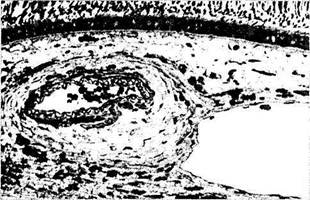

Артерии. Артерии не отличаются от артерий других локализаций и обладают средним мышечным слоем и адвентицией, содержащей коллагеновые и толстые эластические волокна (рис. 3.8.56). Мышечный слой от эндотелия отделен внутренней эластической мембраной. Волокна эластической мембраны переплетаются с волокнами базальной мембраны эндотелио-цитов [496, 959].

Рис. 3.8.56. Микроскопическое строение сосудов хорио-идеи:

а — артерия и вена хориоидеи крупного калибра (стенка артерии обладает толстым средним слоем и адвентицией); б, в — особенности ультраструктуры капиллярных сосудов хориоидеи (/—мембрана Бруха; 2 —эндотелиальная выстилка капилляра; 3 — ядро эндотелиальной клетки; 4 —дубликатура цитоплазмати-ческой мембраны с образованием «пор»)